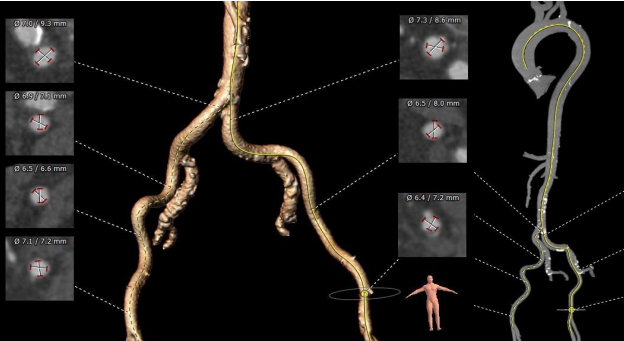

术中影像

主动脉根部造影和冠脉造影+PCI

瓣膜稳定释放和瓣膜释放后左冠显影正常

植入前后跨瓣压差

植入前压差67mmHg,植入后压差2mmHg